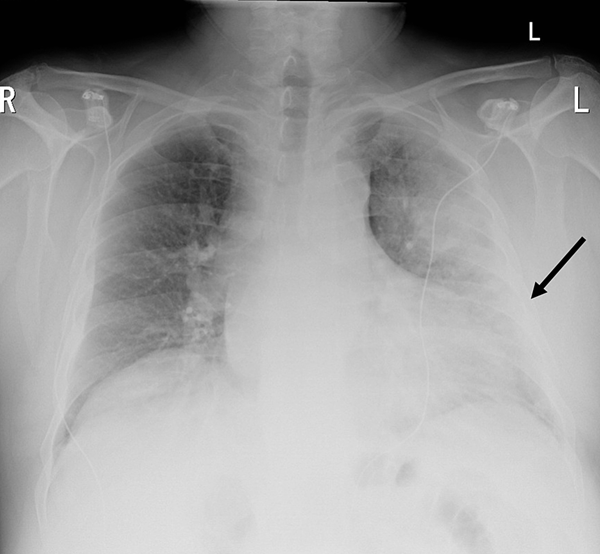

(图2 胸部X线检查)

初始针对COVID-19的治疗包括口服类固醇,注射复合阿莫西林-克拉维酸以及口服克拉霉素治疗继发性胸部细菌感染。在报告CT肺血管造影结果和COVID-19检测阴性结果后,停用类固醇和抗生素,开始使用多西环素治疗非典型肺炎。在应用多西环素治疗治疗的第2天,患者尿中军团菌抗原检测呈阳性。给予口服多西环素治疗14天。感染消退,计划植入永久性起搏器。随访胸部X线显示右侧少量